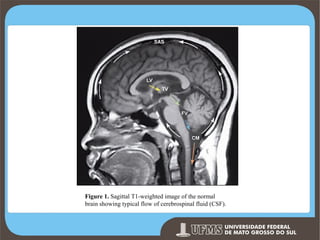

Figure 1. Sagittal T1-weighted image of the normal

brain showing typical flow of cerebrospinal fluid (CSF).